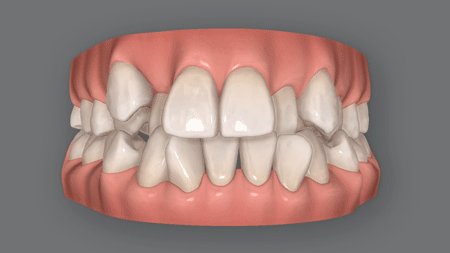

叢生(そうせい)は、ガタガタとかガチャ歯乱杭歯(らんくいば)ともいわれる、歯と歯が重なってデコボコした症状。

程度にもよりますが、不正咬合の中では最も「歯並びがガタガタしている」、そして「清潔感に欠けている」「笑顔がかわいくない」という印象のある症状です。